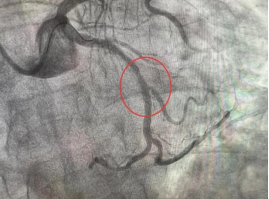

刘先生因“胸痛20天”入院,入院后进行了冠状动脉造影检查,发现其心脏的一支重要血管LCX(回旋支)中段存在弥漫性狭窄,最重处狭窄约90%,确诊为冠心病。随后,内科一病区医生团队为患者实施了冠状动脉支架植入术,术后胸痛症状明显缓解,恢复良好,生活质量显著提升。

(术前) (术后)